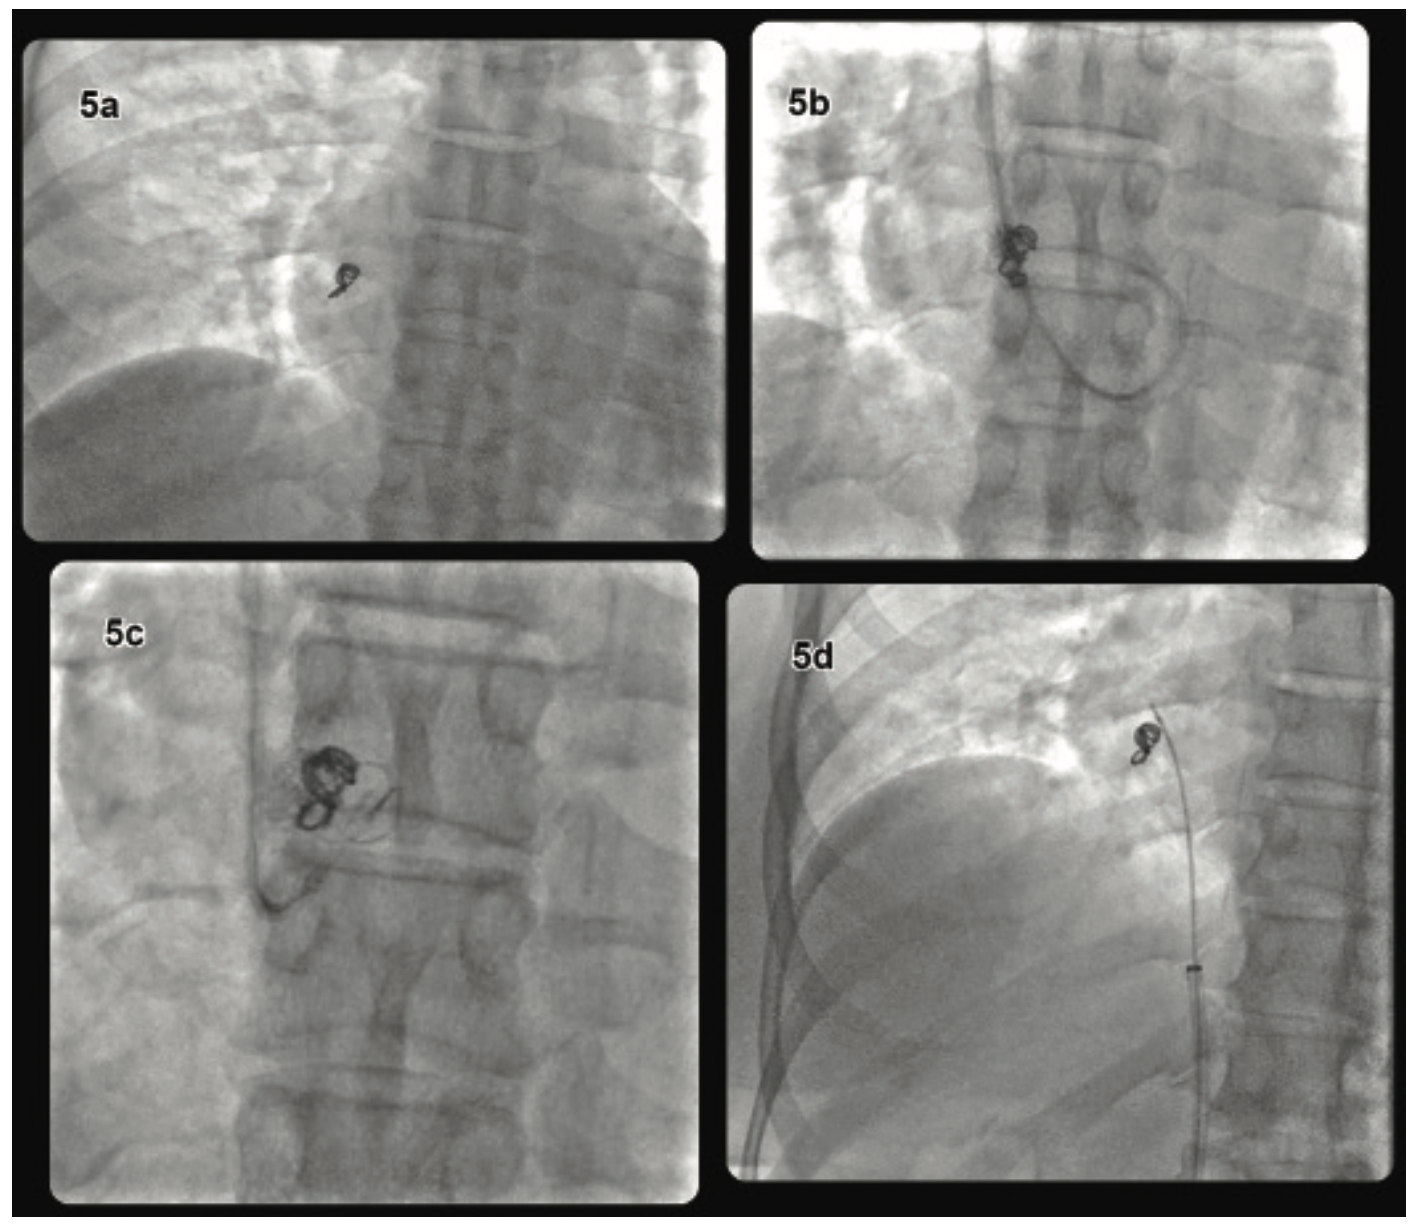

An attempt to retrieve the migrated coil was done via a percutaneous approach. Intravenous access was obtained through the right internal jugular vein and a 5 French (Fr) central venous sheath was inserted. A J-wire was advanced, followed by serial dilatation, and a 9 Fr venous sheath was placed. A Bentson starter wire (Cook Medical) was advanced and a 7 Fr Ansel 2 guide catheter (Cook Medical) was inserted. When the Ansel 2 catheter reached the right atrium, a 25 mm Amplatz Goose Neck snare (Medtronic) was introduced through the guide catheter to try to seize the coil, but this was unsuccessful, despite multiple attempts. Subsequently, a 7 Fr Atrieve 18-30 mm vascular snare set (Argon Medical Devices) was used in an attempt to capture the loop, also without success. Finally, we opted to try a different approach through the right common femoral vein in a similar fashion. Unfortunately, it was also unsuccessful, even after a one-hour attempt (Figure 5).